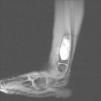

Ante tal hallazgo se derivó a la paciente a Traumatología Infantil que solicitó resonancia magnética (figs. 2 y 3) que mostró niveles de contenido líquido compatibles con un quiste óseo aneurismático. Se procedió a punción-aspiración que resultó negativa para células malignas y con anatomía patológica compatible con quiste óseo aneurismático. La paciente sigue controles evolutivos para valorar posible tratamiento quirúrgico en un futuro.